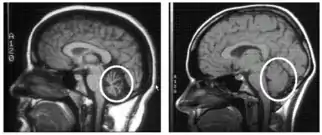

To select an appropriate and accurate diagnostic test for cerebellar degeneration, it is crucial that a range of factors specific to each patient are taken into consideration. These include; the patient's age, acuity of their signs and symptoms, associated neurological conditions, and family history of hereditary forms of cerebellar degeneration.[3] A diagnosis for cerebellar degeneration is regarded after any of the aforementioned signs and symptoms surface. For genetically-classified forms of cerebellar degeneration, genetic testing can be carried out in order to confirm or deny the diagnosis, where this form of testing is only possible if the gene responsible for the cause of the condition is recognised.[25] In saying this, for most conditions the genetic cause of cerebellar degeneration is unidentified, hence these patients cannot proceed with genetic testing.[1] In cases where cerebellar degeneration is acquired, a diagnosis can be established using imaging methods such as computerised tomography (CT scans) and magnetic resonance imaging (MRI), necessary to detect brain abnormalities in patients suffering from cerebellar degeneration.[26]